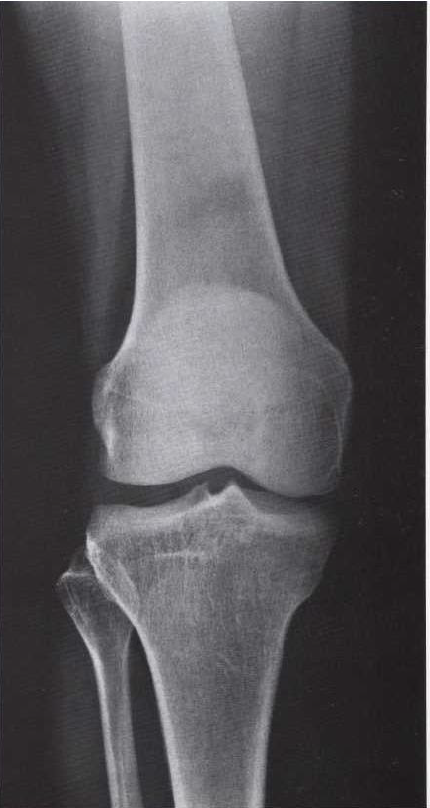

What is this view of the knee? Which views are missing?

AP

MISSING:

Lateral

Intercondylar

Skyline

Medial oblique